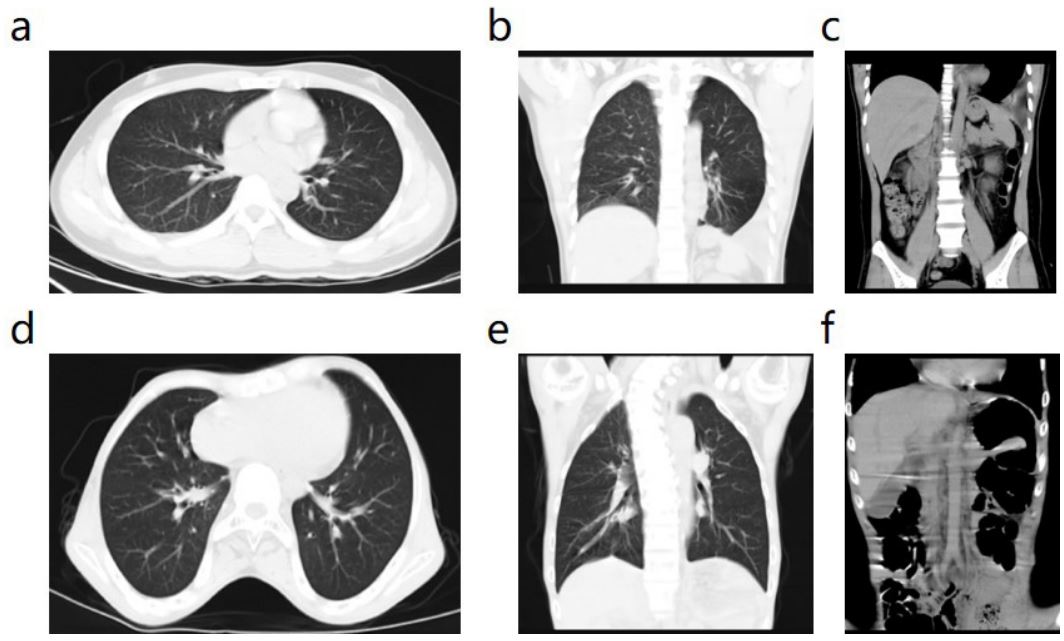

All patients underwent chest and abdominal CT examination before operation. Figure 2 shows the preoperative CT images of one patient with chronic TDH (Case 1) and one patient with acute TDH (Case 2).

Figure 2: Preoperative CT findings in patients with diaphragmatic hernia. (a-c) In Case 1, part of the small intestine, transverse colon, and mesentery vessels herniated into the left thoracic cavity and compressed the left lung. The white arrow showed displacement of the left diaphragmatic crus and a huge diaphragmatic defect. (d-f) In Case 2, most of the gastric cavity herniated into the left thoracic cavity; Part of the intestinal tube in the abdominal cavity was obviously dilated and pneumatoid, which was considered as intestinal obstruction. The green arrow showed the hernia tight rib gastric body.